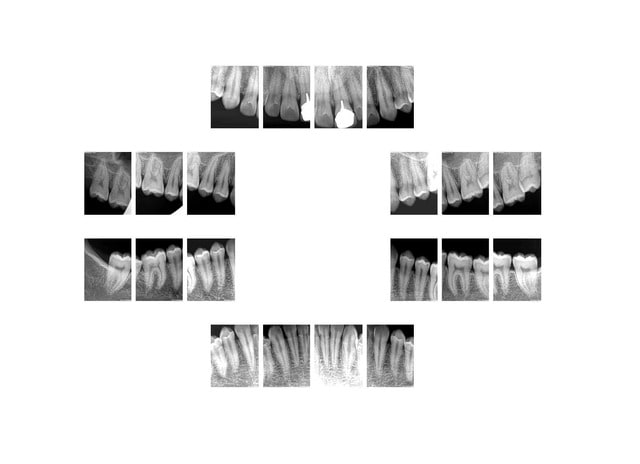

Oui , la meilleure c'est qu'il fait partie de mes cas de radios abusives.

Toutes les radios sont abusives " sauf éventuellement la 21".

Je penses que si tu veux faire un concours tu vas perdre. Patient au smic pas un centime devant lui. Amuses toi. -)))))

1 f8r5uw - Eugenol

2 uqjowx - Eugenol

3 b6buap - Eugenol

4 ax5o6k - Eugenol

5 uxxr26 - Eugenol